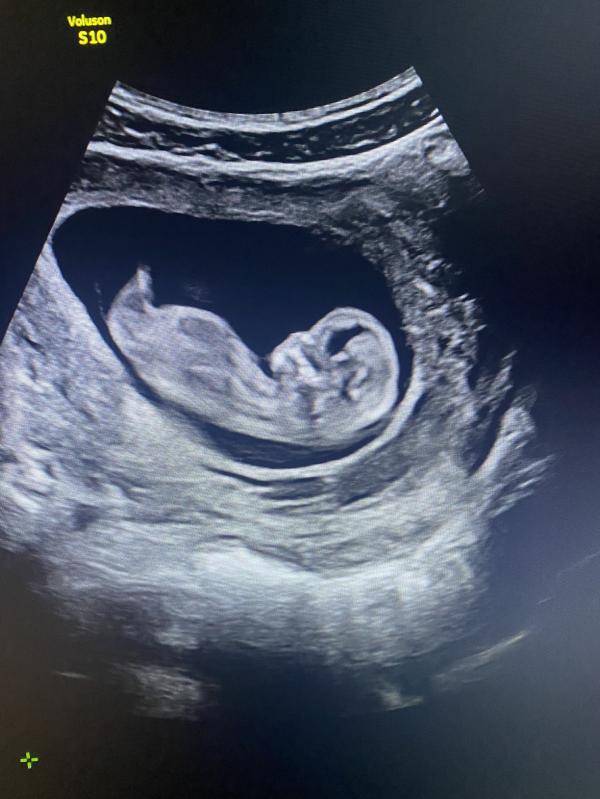

Сегодня была на первом скрининге, все отлично)) Пол не разглядели увы, зато развивается по нормам. Одна проблема- очень низко прикрепился хорион - может ли быть опасно? Стоит переживать?